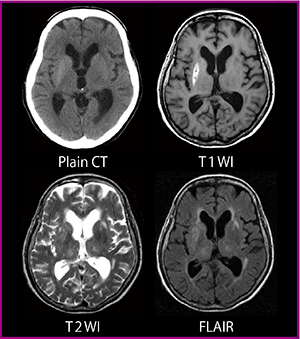

T1強調画像で高信号が認められる症例を,放射線科医はどのように読影しているだろうか。図1(60歳代,女性)は,T1強調画像で基底核に高信号が認められ,CT画像でやや石灰化が見られた症例である。近年,ガドリニウム造影剤の脳への沈着が話題になっているが,造影検査歴のない本症例には当てはまらず,T2強調画像でわずかに高信号となることから基底核石灰化であると考えられる。重量パーセント濃度20〜30wt%の淡い石灰化は,表面効果によりT1強調画像で高信号を示すと言われている。

図1 基底核石灰化(60歳代,女性)